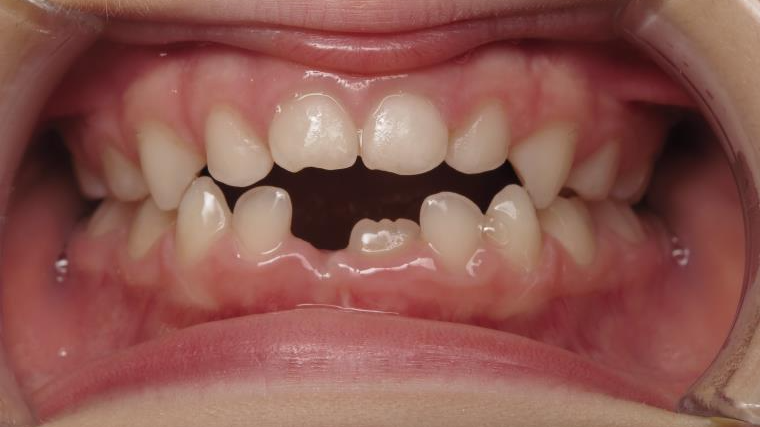

Sélectionnez les différentes étapes du traitement pour comparer et analyser la dentition du cas clinique.

surveillance évolution de la dentition en cours

bilan début et en cours de traitement